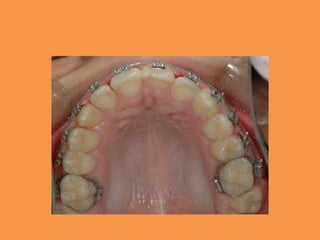

Fig.3a Maxillary arch with adequate

space for impacted incisor before its

surgical exposure

Fig.3b Bracket bonded on labial

surface of tooth no. 21 after

surgical exposure and healing period

Fig.3c Orthodontic traction applied

with 0.016” NiTi wire over